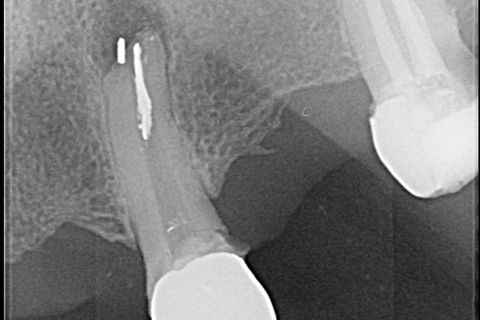

Vista do canal obturado da parte coronária do Cone de Prata

Primeira Separação do Cone de Prata

O retratamento endodôntico começou com o acesso à câmara pulpar usando uma Broca Dental Predator Turbo (Angelus - Londrina - Brasil). O cimento em torno da haste do cone de prata foi removido com uma ponta ultrassônica E7D (Helse Ultrasonic - Brasil) (Figura 2). Após a exposição da parte coronária do cone de prata, uma E5 – Ponta Cônica Longa Ultrassônica (Helse Ultrasonics - Brasil) foi usada para vibrar o corpo do cone de prata. Embora a baixa potência ultrassônica ajustada em 15%, ocorreu uma separação (Figura 3). Devido à falta de adaptação do material da obturação no terço apical, parte do fragmento de cone de prata foi removida da lesão periapical.